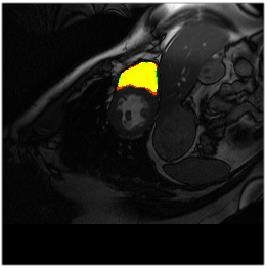

Deep Convolutional Neural Networks (DCNNs) are used extensively in biomedical image segmentation. However, current DCNNs usually use down sampling layers for increasing the receptive field and gaining abstract semantic information. These down sampling layers decrease the spatial dimension of feature maps, which can be detrimental to semantic image segmentation. Atrous convolution is an alternative for the down sampling layer. It increases the receptive field whilst maintains the spatial dimension of feature maps. In this paper, a method for effective atrous rate setting is proposed to achieve the largest and fully-covered receptive field with a minimum number of atrous convolutional layers. Furthermore, different atrous blocks, shortcut connections and normalization methods are explored to select the optimal network structure setting. These lead to a new and full-scale DCNN - Atrous Convolutional Neural Network (ACNN), which incorporates cascaded atrous II-blocks, residual learning and Fine Group Normalization (FGN). Application results of the proposed ACNN to Magnetic Resonance Imaging (MRI) and Computed Tomography (CT) image segmentation demonstrate that the proposed ACNN can achieve comparable segmentation Dice Similarity Coefficients (DSCs) to U-Net, optimized U-Net and hybrid network, but with significantly reduced trainable parameters due to the use of full-scale feature maps and therefore computationally is much more efficient for both the training and inference.